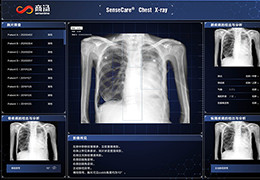

工作流智能。

在这里,先进的智能功能自动执行手动任务和工作流程步骤,以简化流程,提高技术人员工作效率,节省时间和金钱,并增强患者护理。

自动化设备定位和患者姿势确认可优化放射科技师的效率并加快工作流程。

自动技术选择可改善影像一致性并支持辐射剂量控制。

通过任务自动化功能改进感染控制,使放射科技师不再与潜在感染患者直接接触。

分析智能。

这些功能利用数字控制面板分析运营、业务和临床绩效。

使管理员能够跟踪关键参数,包括平均曝光率、拒绝的影像和探测器统计信息。

帮助确定需要改进的方面,支持为员工和部门制定适当的改进计划。